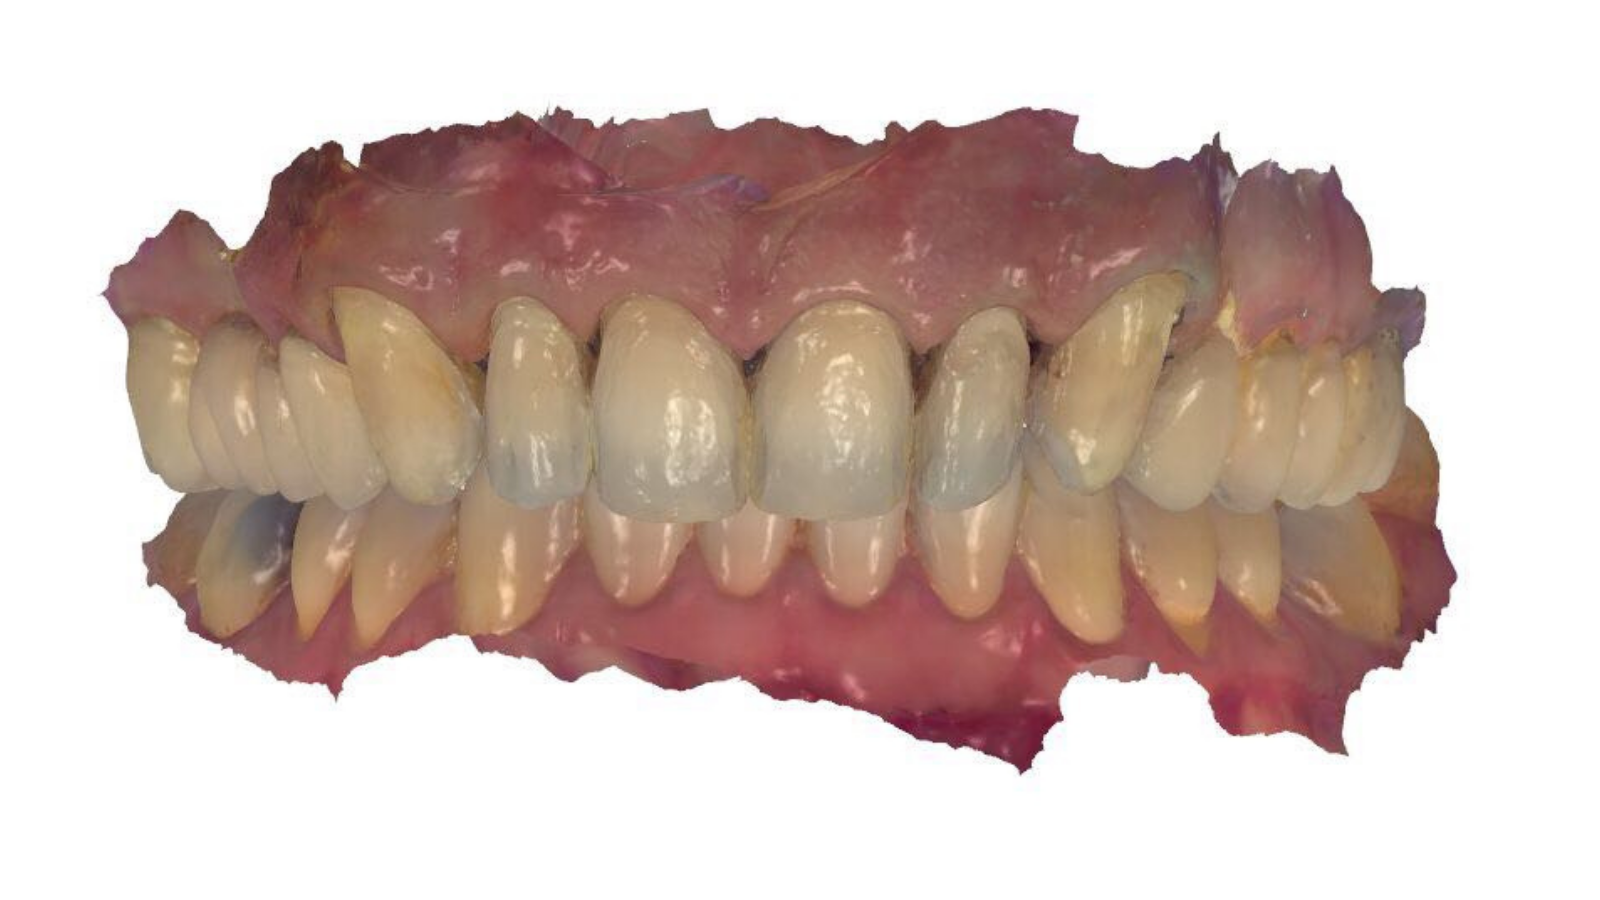

Réhabilitation esthétique après orthodontie : full-zircone & disilicate de lithium

Une jeune patiente arrive en fin de traitement orthodontique pour un déficit esthétique.

La difficulté réside dans la réalisation de prothèses différentes dans le même secteur : jongler avec la full-zircone et le disilicate de lithium.

Ce challenge fut le sujet de mon mémoire du DU d’esthétique de Strasbourg en 2008.

L’expérience et l’investissement dans le digital depuis 2017 rendent le résultat plus prévisible.

Images :